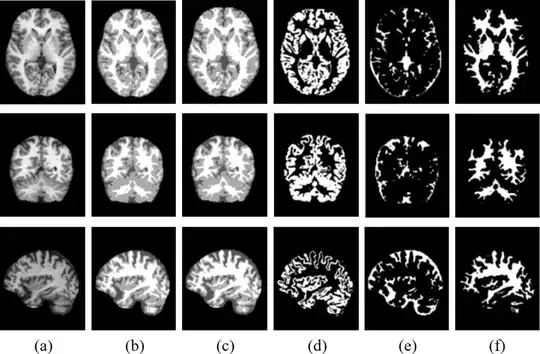

Image of segmented brain Image from Lee et al. (2020)

McClure et al. (2019) describes

a Bayesian deep neural network (DNN) for predicting FreeSurfer segmentations of structural MRI volumes, in minutes rather than hours.